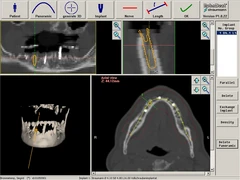

Surgical navigation for 2D (LAT/AP) C-arm-based spinal surgery (2018)

Project: Surgical navigation for C-arm-based spinal surgery

Scientists involved: WW, EL, SH, NS, JZ, BL, BZ, JZ, SS, CS, Tim Lueth

Objective: The objective was to develop a very fast, efficient, and easy-to-use navigation system for spinal surgery. Robust, reusable electromagnetic instruments must be used. The system must offer a way to co-register C-arm projection image data and CT/MRI-based volumetric image data.

Results: The Integrated Navigation Tracking & Control System received the 2019 Spine Technology Award from the North American Spine Society (NASS) in September 2019.

Selection of our publications:

https://www.odtmag.com/contents/view_breaking-news/2019-09-23/nass-news-joimax-wins-2019-spine-technology-award/

The system is certified and in regular clinical use worldwide.